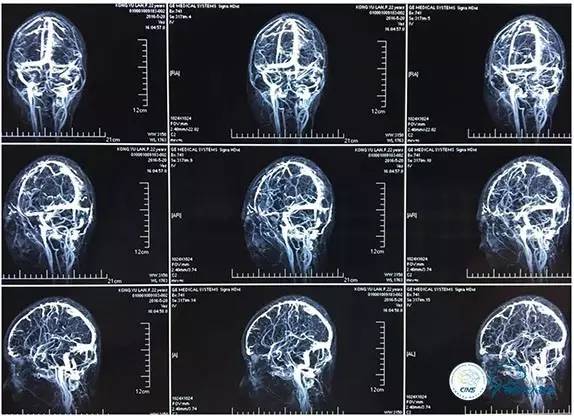

MRV

右侧ICA正位

右侧ICA侧位

右侧ICA斜位

左侧ICA正侧位

右侧VA正位

左侧VA正侧位

右侧ICA造影正侧位

右侧ICA造影斜位

右侧ICA正侧位

左侧ICA斜位

左侧VA正斜位

术中右侧ICA造影

右侧ICA斜位及窦内造影

窦内造影及路图